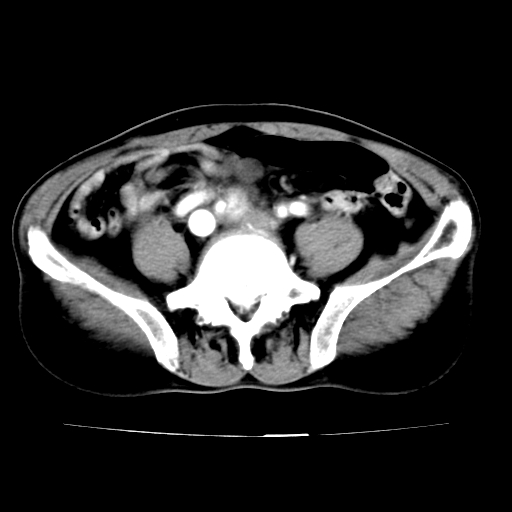

标题: V0243:右髂总动脉瘤附壁血栓形成?破裂?动静脉瘘? [打印本页]

标题: V0243:右髂总动脉瘤附壁血栓形成?破裂?动静脉瘘?

男,75岁,腹痛月余,彩超发现脐周腹主动脉异常回声。临床诊断:腹主动脉瘤。

ct诊断:右骼总动脉囊性动脉瘤并瘤内附壁血栓形成,与下腔静脉之间形成动静脉瘘。

请问各位老师:能排除动脉瘤破裂的可能吗?

各位老师注意到下腔静脉的充盈缺损了吗?注意到动静脉漏了吗?

当时是扫描的标准动脉期,可是下腔静脉与腹主动脉同步强化且幅度一致。所以我想动静脉瘘是存在的。